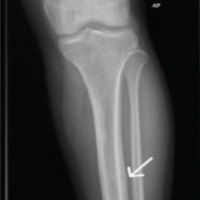

We are presenting 35-years-old free medically, active soldier referred to the orthopedic clinic from family medicine after noticing abnormal incidental findings on X-rays (Fig. 1-4).

On inquiring him, he doesn’t recall any problem during his childhood and performing his military duties. On clinical examination of the patient, he had characteristic features of patellar absence with prominent femoral condyles and hollow sulcus as per computed tomography (CT) both knees (Fig. 5,6).

He has good quadriceps and hamstring power 5/5. No other abnormalities were detected in his upper and lower limbs. Potential biomechanical adaptations that help to maintain normal gait and joint kinematics in this patient with congenital absence of the patella, specifically mechanisms that prevent knee hyperextension. This may include strengthening or altered recruitment of surrounding musculature (e.g., hamstrings, hip flexors, gastrocnemius), and modified joint alignment or ligament tensioning within normal compare to other studies. Both static postures and dynamic loading scenarios, for example, walking and stair climbing, have been stable movements, which are normally enhance quadriceps efficiency by increasing the moment arm and increased hamstring stress due to compensatory function in absence of the patella (Fig. 5). His blood parameters of liver function test, renal function test, and bone profile and labs are all normal (Table 1). Patient’s hip joints demonstrated a normal range of movement and his ankle joints were also normal. The rest of her musculoskeletal exam was also normal. His cardiovascular, neurological, and abdominal examinations were all normal (Fig. 5). CT chest, abdomen, and pelvis showed no osseous or visceral abnormal. (Fig. 7 & 8).